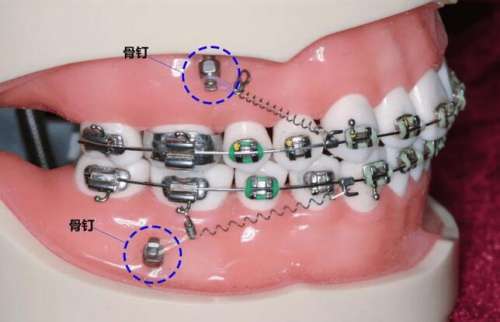

打骨釘是指在手術(shù)中將一根金屬釘子穿過(guò)病人頜骨,在外部固定器的幫助下,強(qiáng)制矯正頜骨的錯(cuò)位,并保持正確的位置。這種方法在調(diào)節(jié)骨性嘴凸方面有著廣泛的應(yīng)用。

打骨釘是將金屬釘子通過(guò)手術(shù)的方式打進(jìn)骨骼中,然后通過(guò)緊固器將釘子與其他金屬部件連接在一起,以固定斷骨或者矯正骨骼的位置。打骨釘?shù)姆绞椒譃閮?nèi)固定和外固定兩種,內(nèi)固定是指將釘子直接打進(jìn)骨骼內(nèi)部,而外固定則是將骨釘釘在骨外部,通過(guò)金屬桿或者線條將骨骼固定住。